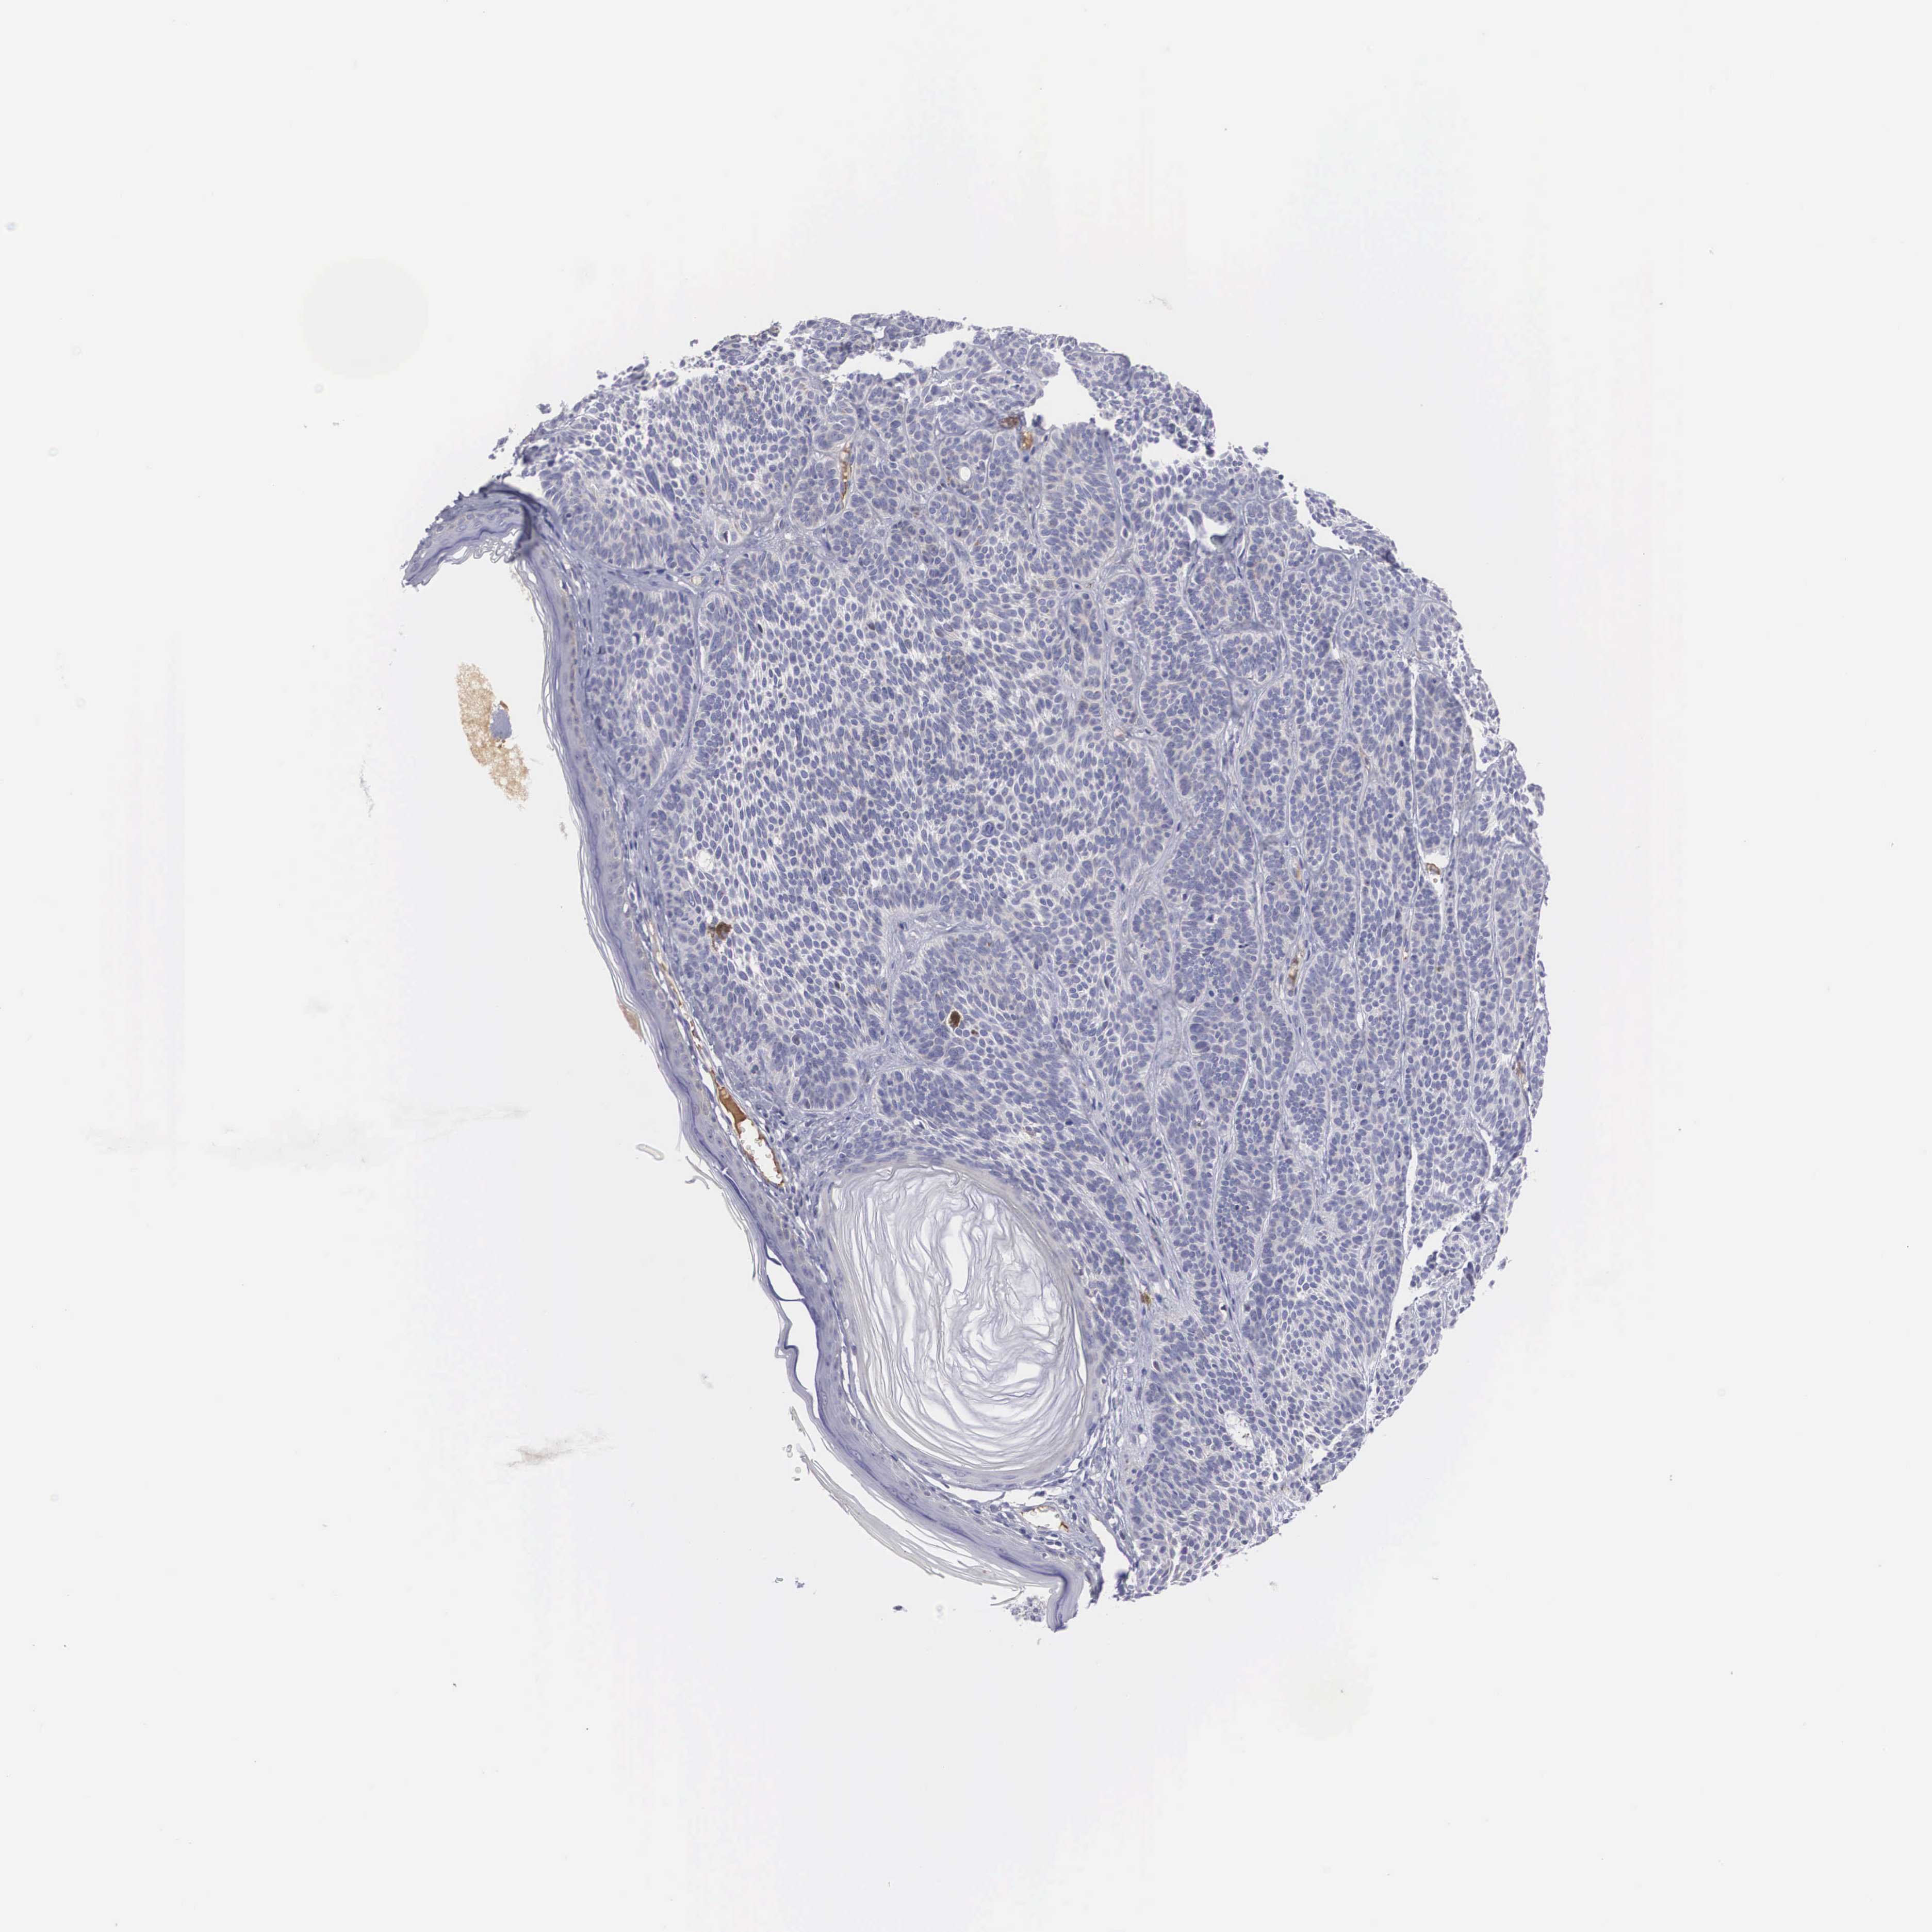

SKIN CANCER - Protein expressioni

A mouse-over function shows sample information and annotation data. Click on an image to view it in a full screen mode. Samples can be filtered based on level of antibody staining by selecting one or several of the following categories: high, medium, low and not detected. The assay and annotation is described here.

Antibody stainingi

Antibody staining in the annotated cell types in the current human tissue is reported as not detected, low, medium, or high, based on conventional immunohistochemistry profiling in selected tissues. This score is based on the combination of the staining intensity and fraction of stained cells.

Each image is clickable and will lead to virtual microscopy that enables deeper exploration of all samples and also displays staining intensity scores, fraction scores and subcellular localization as well as patient and tissue information for each sample.

Antibody HPA000251

Staining

High

Medium

Low

Not detected

Intensity

Strong

Moderate

Weak

Negative

Quantity

>75%

75%-25%

<25%

None

Location

Nuclear

Cytoplasmic/membranous

Cytoplasmic/membranous,nuclear

Squamous cell carcinoma, NOS